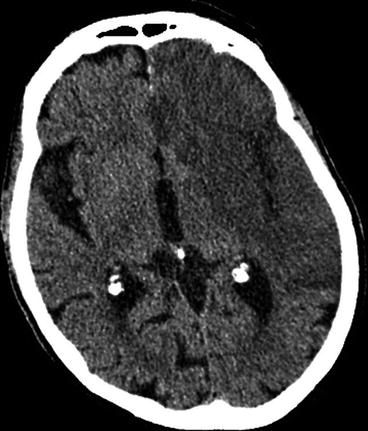

Computed Tomography Radiology Key Computed tomography modern radiology is a free educational resource for radiology published online by the european society. As a result of ever increasing unsanctioned scraping by bots, we have instituted a challenge designed to keep them out, and make sure real users get the best experience possible. if you're not a bot, you shouldn't see this error. if it persists, please contact [email protected] and we'll help to unblock you. Computed tomography (ct) is defined as a medical imaging technique that measures the intensity attenuation of x ray beams from multiple orientations to create cross sectional images, utilizing a scanner comprised of an x ray source and a series of detectors. The evolution of x ray computed tomography (ct) has been based on the discovery of x rays, the inception of the radon transform, and the development of x ray digital data acquisition systems.

Computed Tomography Radiology Key Computed tomography (ct) is defined as a medical imaging technique that measures the intensity attenuation of x ray beams from multiple orientations to create cross sectional images, utilizing a scanner comprised of an x ray source and a series of detectors. The evolution of x ray computed tomography (ct) has been based on the discovery of x rays, the inception of the radon transform, and the development of x ray digital data acquisition systems. It begins by introducing ct and comparing it to conventional radiography. ct provides more accurate diagnostic information by reconstructing 3d structures from multiple 2d projections, unlike conventional radiography which produces 2d shadow images. The main advantages of ct over conventional radiography are with ct, the superimposition of structures is minimized with ct, the ability to differentiate small differences in density according to their individual shades of gray is maximized. Purpose: we provide a review of the key computed tomography (ct) technologies developed since the late 1980s and offer an overview of one of the future technologies under development. the focus of this review is mainly on the hardware and system development. This article examines the key physical principles and technical features of the ct scanner, highlighting significant developments in ct technology that have led to the creation of helical, multidetector, cone beam, portable, dual energy, and phase contrast ct.